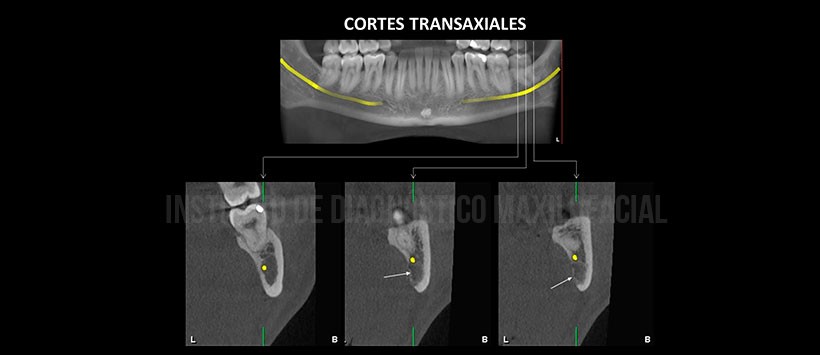

En los cortes multiplanares (figura 2) y transaxiales de la pieza 3.7 (figura 3), se aprecia adelgazamiento y depresión de la tabla ósea lingual de limites definidos y corticalizado a nivel de la escotadura antegonial que se extiende desde el reborde basal mandibular hasta la cortical inferior del conducto dentario inferior